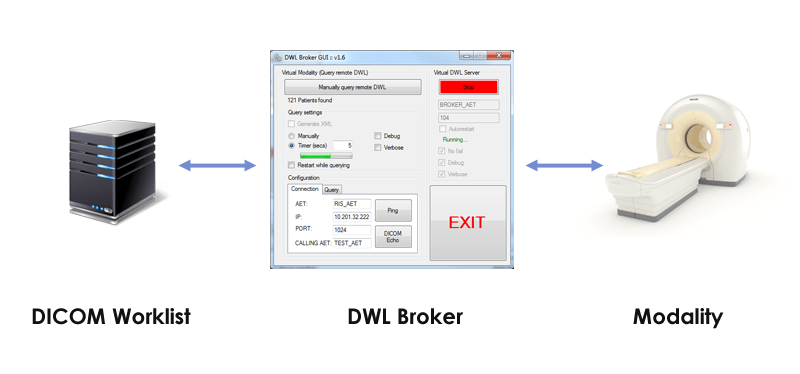

Лазерная камера сетевая для печати изображений на пленке стандарт dicom